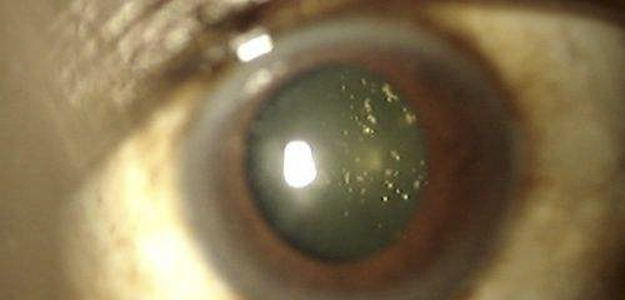

A:飛蚊症是指眼前有飄動的黑影,尤其是看白色背景的時候症狀更加明顯,同時有時候有些人會伴有閃光感,眼前一亮一亮的症狀,引起的原因主要是玻璃體液化和後脫離。絕大多數的飛蚊症都是生理性,但是有大約20%的飛蚊症,可能是病理性,具有威脅視力下降的情……

A:眼前出現飛蚊的症狀往往是因為玻璃體發生了液化、變性和混濁,通常情況下玻璃體的混濁,比較多見於近視眼的人和年歲比較大的中老年人,還要特別重視的一個問題是當眼底有病變發生的時候,也會出現玻璃體的混濁、玻璃體混濁的加重,這時候眼前飛蚊的症狀需要做……

A:眼睛裡有飛蚊的現象主要是因為玻璃體發生了液化、變性和混濁,玻璃體原本在眼睛裡邊是一個膠凍狀的結構,由於近視眼以及中高度近視或者年齡過大了,中老年人就會出現玻璃體的液化、變性和混濁,這種情況下很難通過任何治療,將已經液化的玻璃體恢復到膠凍狀的……